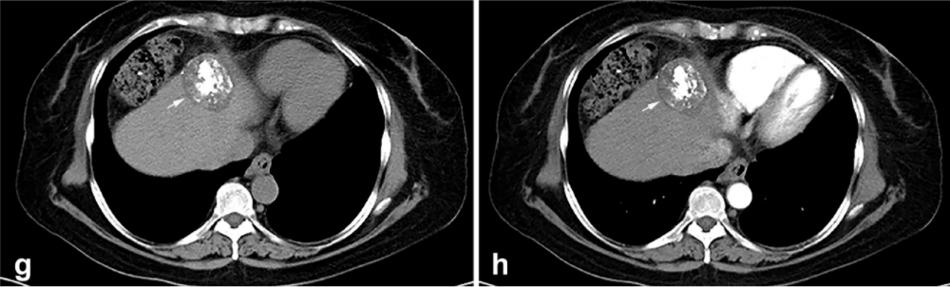

背景:由于一些原因,位于膈肌附近的腫瘤的熱消融在技術(shù)上具有挑戰(zhàn)性。首先,術(shù)中計算機掃描和超聲檢查無法清晰顯示射頻消融/微波消融切緣。第二,消融過程中不利的針分布和過熱可能導致肝包膜破裂,并對膈、肺和心臟造成嚴重損傷。第三,即使使用人工腹水,仍有9~22%的患者因肝周粘連或腫瘤位置靠近肝表面而導致膈肌熱損傷。冷凍消融可能是毗鄰膈肌的HCC的一種有前途的治療方法,因為在消融過程中使用CT和US可以很好地顯示腫瘤邊緣。盡管一些研究評估了在高危區(qū)域使用冷凍消融治療HCC,但很少有研究針對膈肌臨近區(qū)域。

① 術(shù)后 1 月腫瘤治療反應:冷凍消融術(shù)后一個月腫瘤疾病控制率達95.9%。

③ 總生存曲線和局部腫瘤進展曲線:冷凍消融后中位生存時間為 27.3 個月,中位局部腫瘤進展時間為 20.9 個月。